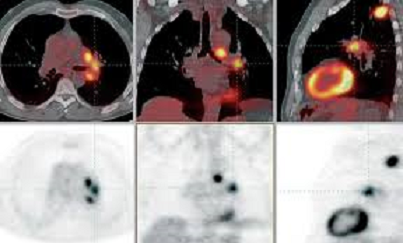

Es el único sistema con tecnología híbrida simultánea, que permite desde una misma plataforma, detectar y localizar tumores en tejidos blandos, gracias a la superioridad en la calidad de imágenes y detalle anatómico de la Resonancia Magnética, mientras que el PET investiga al mismo tiempo el tejido a nivel celular y metabólico, con una capacidad única para la obtención de imágenes, incluso en órganos en movimiento como el corazón, riñones o pulmones.

Las bondades de este equipo se destacan principalmente en el área oncológica, gracias a la información anatómica que aporta y la posibilidad de estudios de múltiples parámetros, sin embargo, tiene alta eficacia en casos de demencias, pacientes con Parkinson, epilepsia, enfermedades degenerativas, cardiología y de manera muy importante en la evaluación de tumores cerebrales, esto por la superioridad de la RM en la valoración de lesiones en el cerebro.